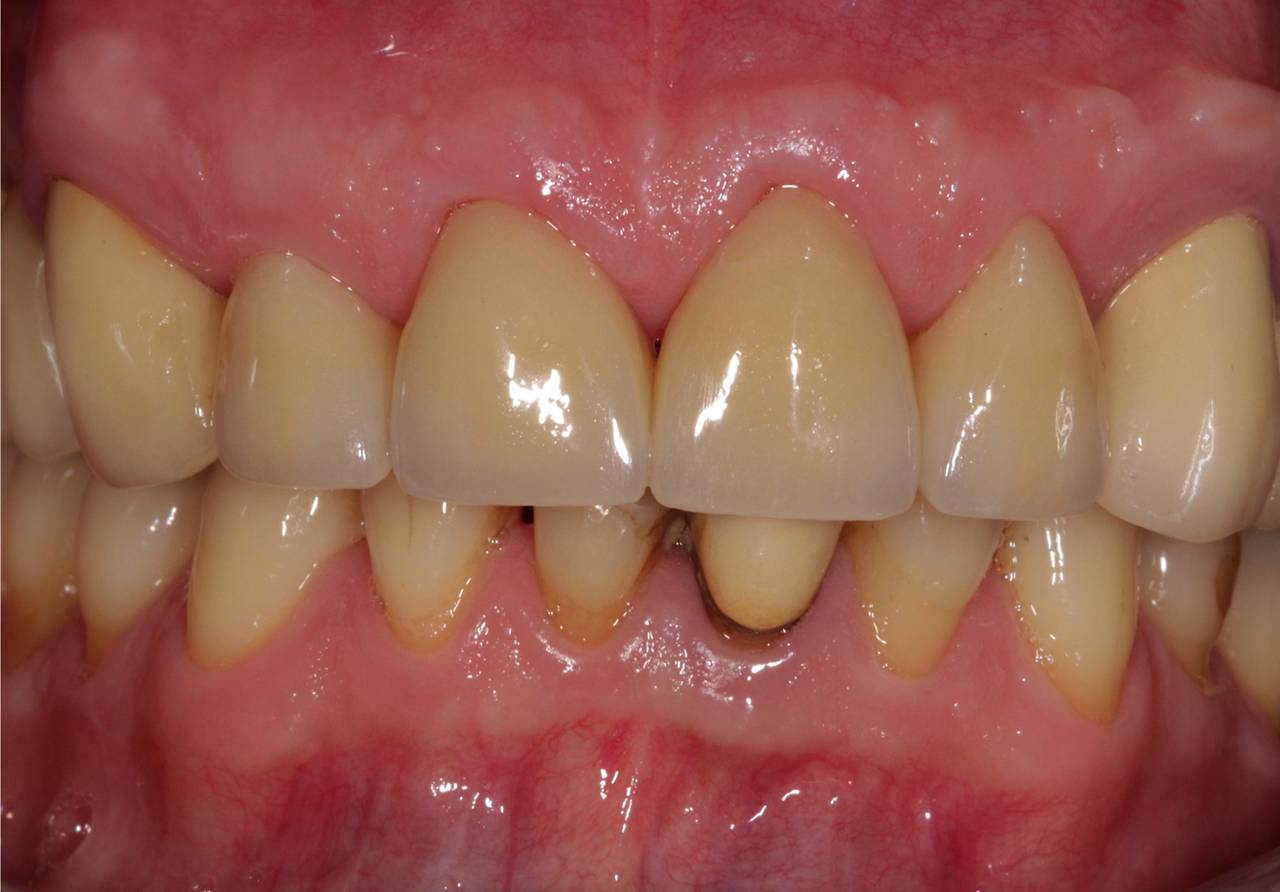

Fertige Arbeit